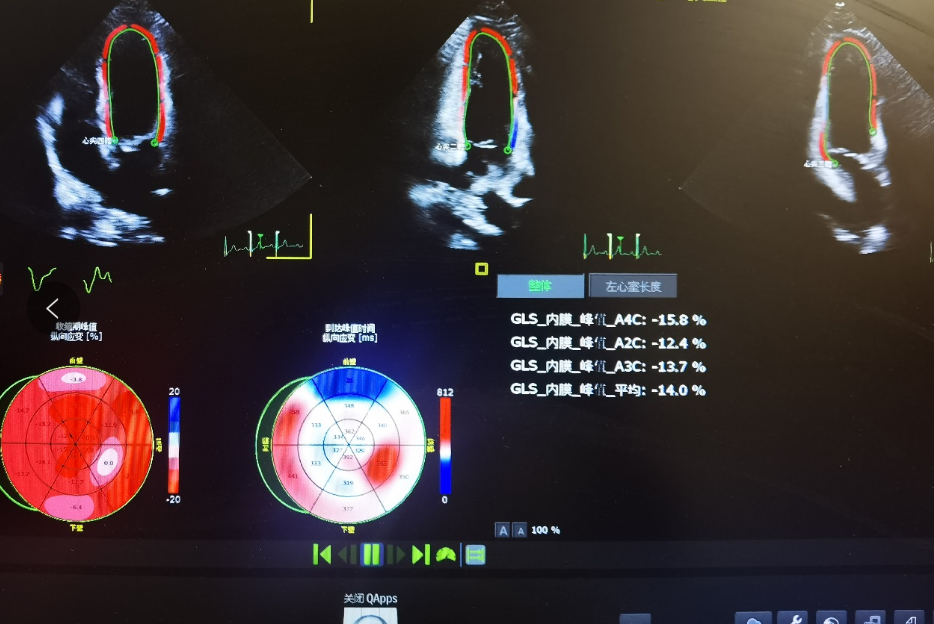

经过检查发现,小刘的左心室长轴应变绝对值只有14%。明显低于正常18%的界限。在袁主任的建议下小刘做心肌酶谱检查后发现血清肌钙蛋白0.573,明显高于0.03的正常上限,后被心内科医生确诊为心肌炎,后续得到有效治疗,目前已得到好转。

“目前的研究结果发现斑点超声心动图技术能够以高分辨率定量检测心脏心肌功能,准确反映心肌机械变形能力,不受心肌运动和周围组织牵拉的影响,在心肌受损后,左心室长轴应变的绝对值会降低,可以发现比较早期的心肌损伤,对判断早期心肌炎具有较高的灵敏度,对正确及时诊断新冠相关心肌炎有非常大的帮助”袁振茂主任说,“本周我们对新冠感染后的胸闷胸痛症状的患者做了该项检查,7人中有2人出现左心室长轴应变异常,之后临床均诊断为心肌炎。”